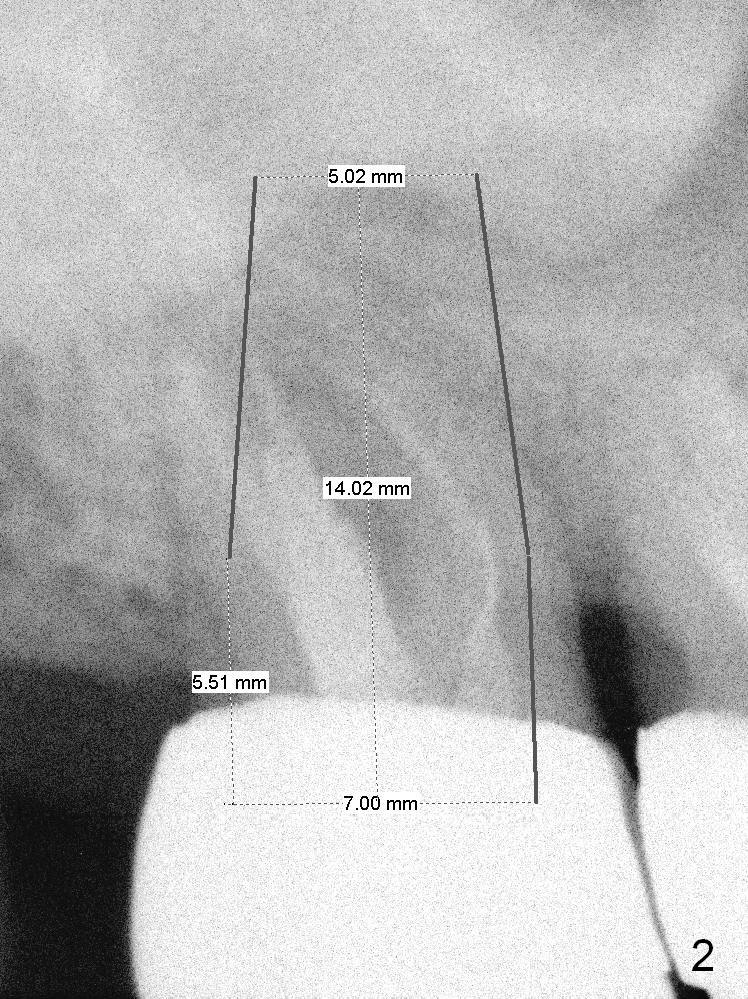

A 59-year-old man is a bruxer, fracturing the teeth #8 and 9.  Now the tooth #2 seems to have fractured (Fig.1).  Since the apices appear to protrude into the sinus, either 7x14 mm tissue-level (Fig.2) or 6.9x10 mm bone-level (Fig.3) implant will most likely penetrate the sinus floor (red dashed line).  To protect the sinus membrane, PRF membrane or plug (blue curved line) is to be placed prior to bone graft (yellow circles) and implant placement.  Prepare Magic Expanders and Magic Sinus Lifter.  Clindamycin will be used after extraction.  Since the roots of the upper 2nd molar usually fuse, prepare large gauzes for hemostasis.  Check the buccal and palatal walls for any defect.  Start osteotomy away from the defective wall.  Place the remaining PRF membrane for wall repair before bone graft.  Set stopper 2 mm short of the intended bone-level implant length.